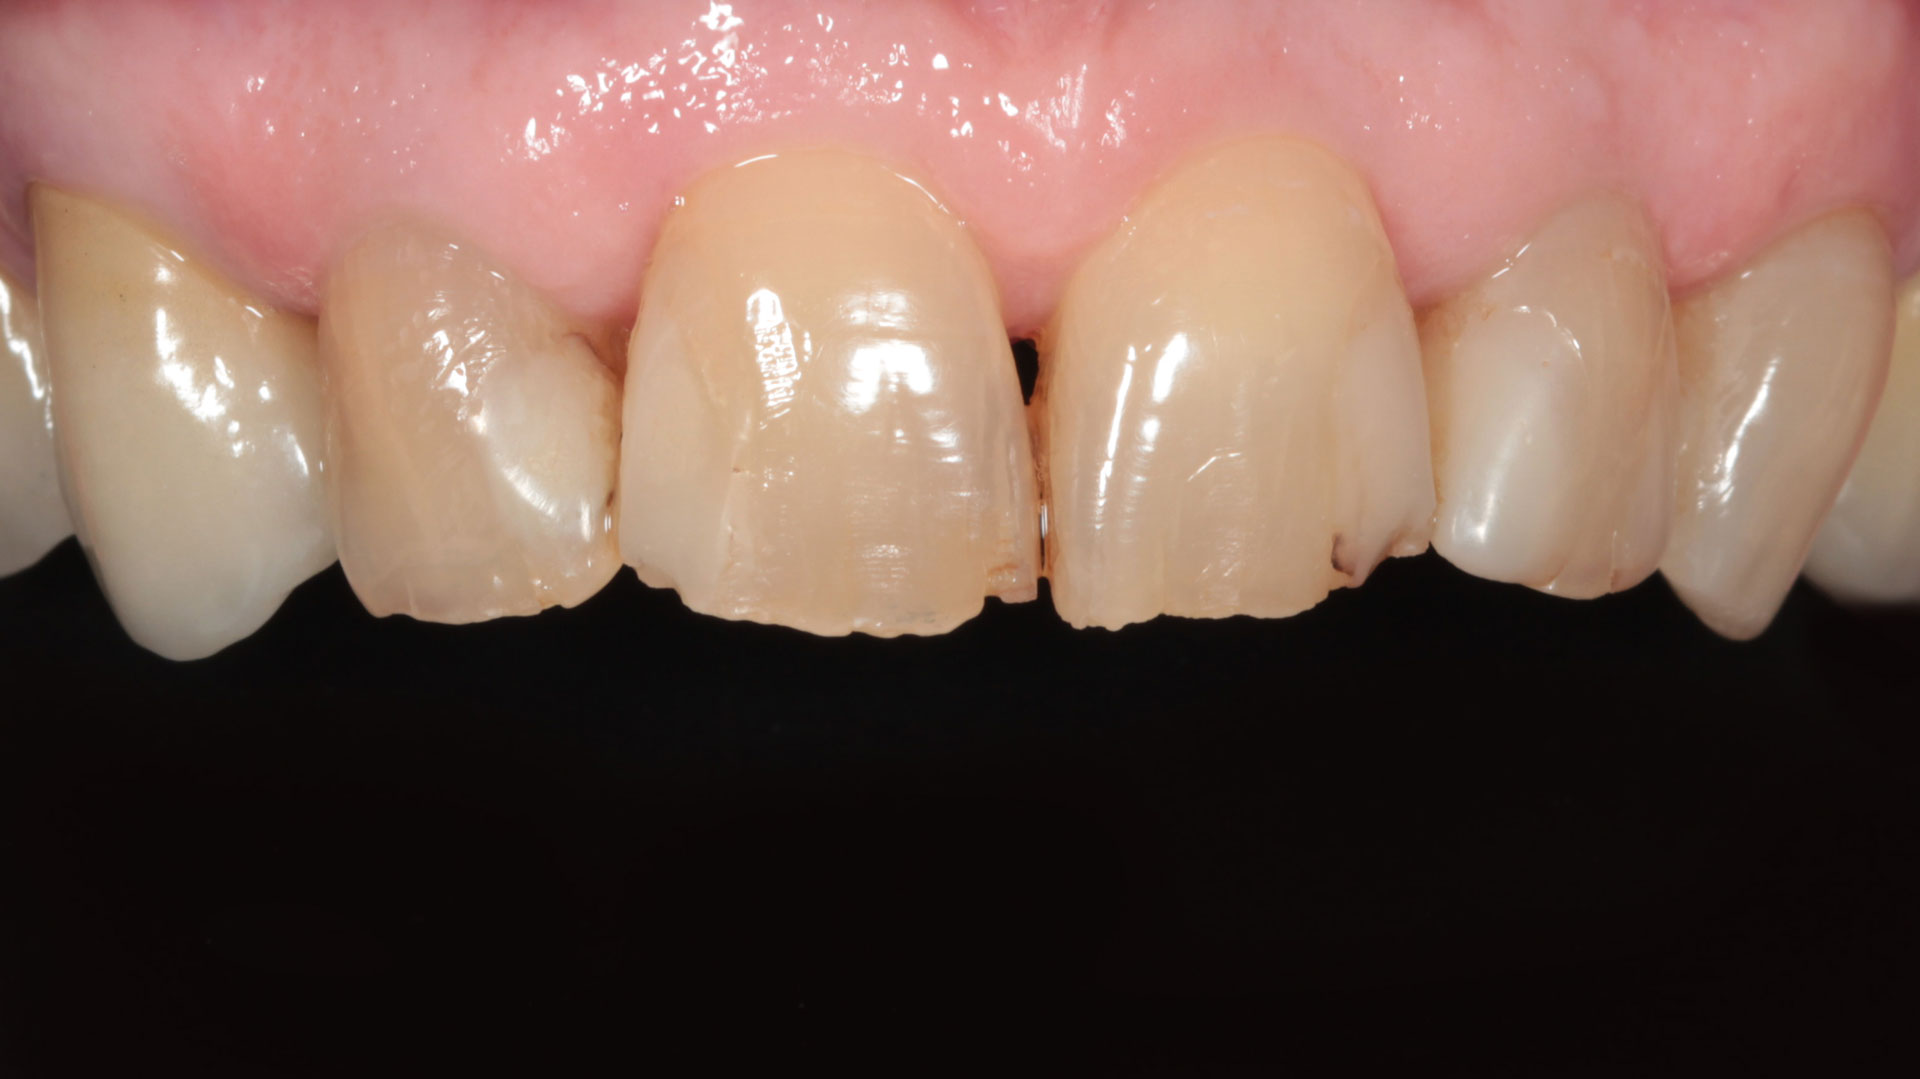

FACCETTE DENTALI

La sottile differenza.

Per migliorare l’aspetto del sorriso, renderlo più luminoso e solare.

- Preparazioni dentali ultra-conservative

- Utilizzo di ceramiche ad alta valenza estetica

SBIANCAMENTO DENTALE

Discromie diverse richiedono diversi sistemi di sbiancamento

Riconoscere il tipo di discromia permette di creare il giusto piano di sbiancamento, dalla sola seduta di igiene orale con lucidatura ad aria, allo sbiancamento vero e proprio con gel sbiancante, fino alla soluzione protesica con faccette o corone.